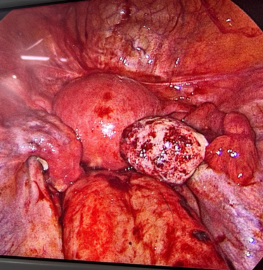

27yr female with acute pain abdomen for 2days. Admitted. Pregnancy test positive USG showed mild to moderate fluid in abdomen. Haemoglobin was decreasing. Decided to do diagnostic laparoscopy. After entering into the a dome there was approx 1 lit blood inside. Continuous bleeding from right ovarian cyst. Cauterisation and biopsy done.